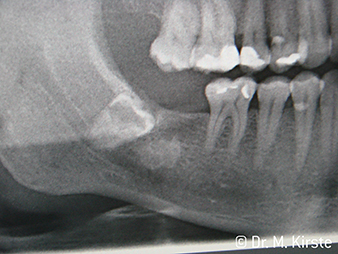

W&H X-Ray

Abbildung 6: Patientenbeispiel: Der verlagerte Zahn 48 ...